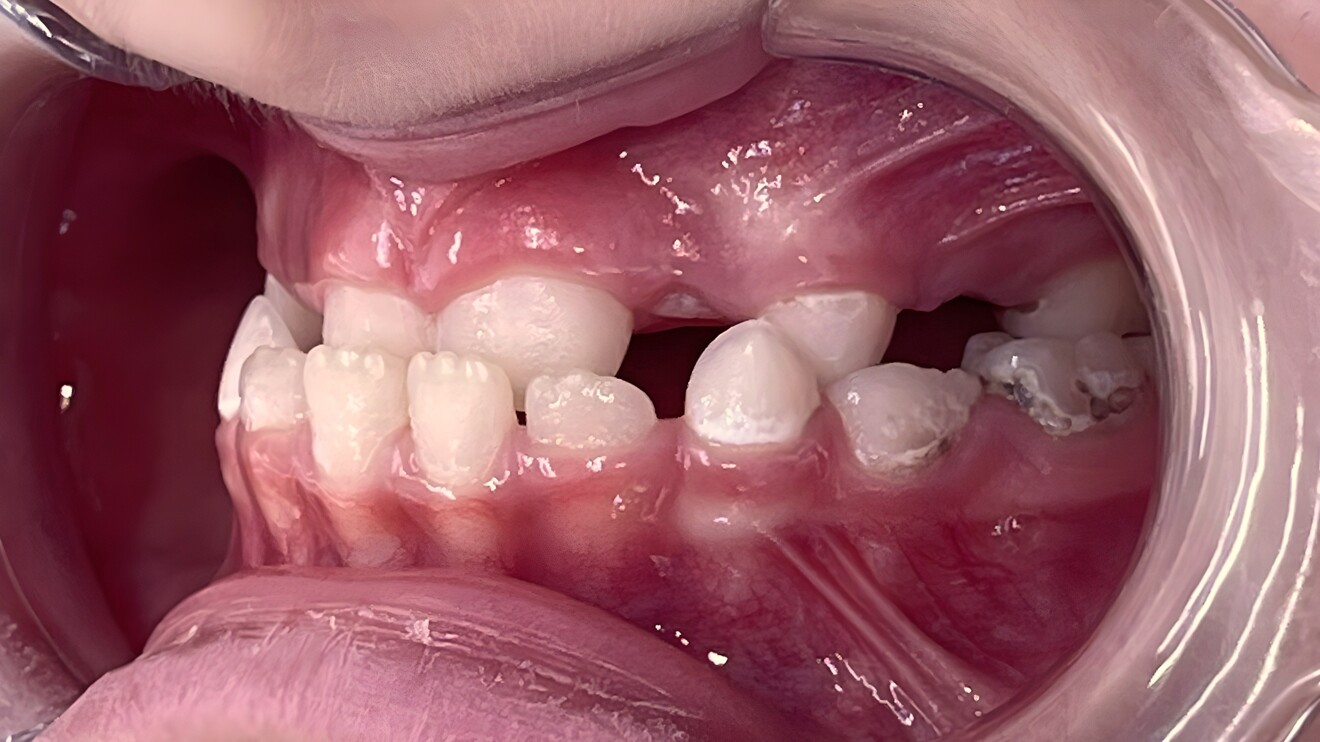

Figs. 2d–h: Post-treatment records. Intra-oral photographs.